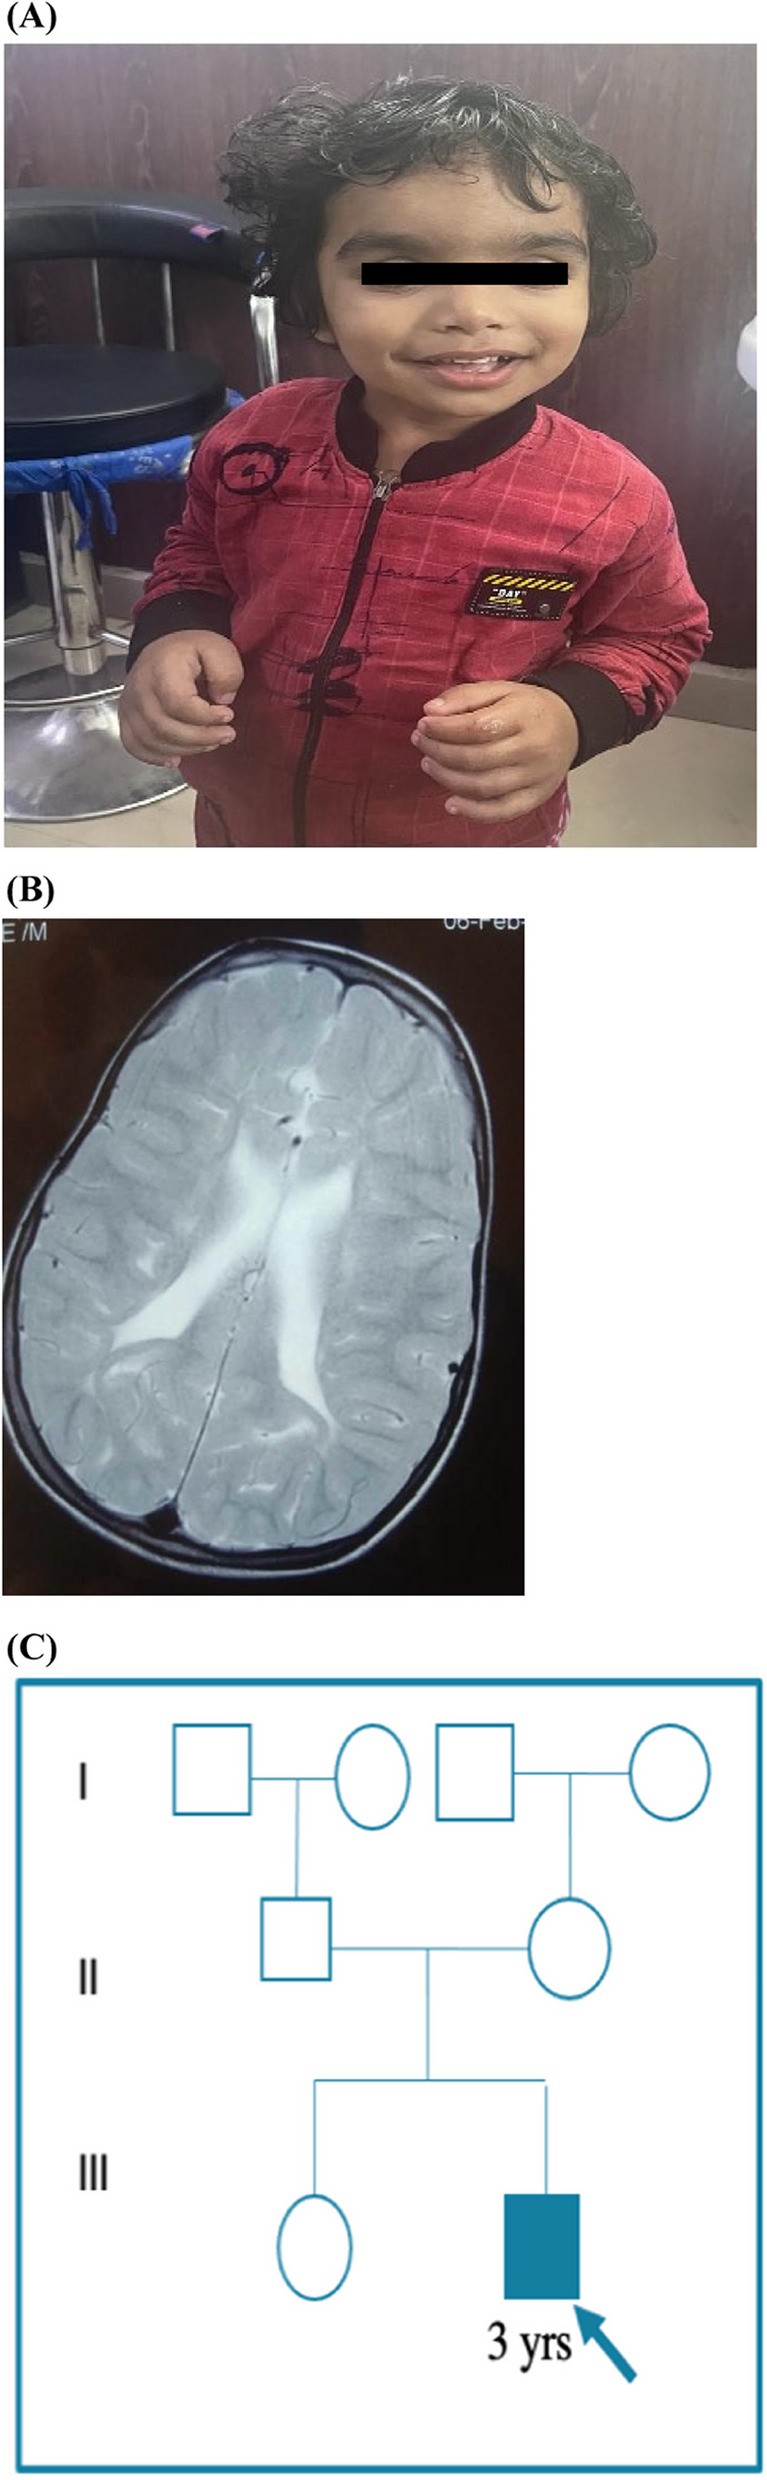

Background: DeSanto-Shinawi Syndrome (DESSH) is a rare neurodevelopmental disorder characterized by intellectual disability, behavioral abnormalities, and distinctive dysmorphic features, linked to likely pathogenic/pathogenic variants in the WAC gene. We report the first documented case of DESSH in India, identified in a 3-year-old male presenting with global developmental delay and coarse facies.

Results: Exome sequencing revealed a novel heterozygous nonsense likely pathogenic variant (c.1661 C>A(p.Ser554*)) in the WAC gene, expanding the genotypic spectrum associated with this condition. We employed computational methodologies to understand the effects of this novel variant on protein structure and function. In-silico prediction score suggested protein truncation due to the c.1661 C>A (p.Ser554*) variation in the WAC gene, expected to result in a loss of normal protein function.